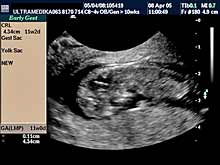

A) I trimestar do 14

nedelje gestacije

(3 meseca + 2 nedelje)

- GENETSKI SONOGRAM (2 - 3 ½ meseca):

- Otkrivanje ultrazvučnih markera na postojanje hromozomskih

anomalija ploda (SKRINING na ANEUPLOIDIJE). Ovaj genetski sonogram

treba uraditi dva puta u intervalu od 9 do 14 nedelje gestacije uz

biohemijsku proveru iz krvi trudnice nakon tačne ultrazvučne procene

veličine ploda. Genetski sonogram sam isključuje oko 88% trizomija,

a udružen sa biohemiskim analizama se isključuje oko 98%

aneuploidija.

- Prva procena i otkrivanje krupnih anatomskih anomalija ploda

koje ne moraju pratiti hromozomske anomalije.

NAPOMENA:

Ultrazvučni markeri za aneuploidije nestaju nakon I

trimestra trudnoće. Nakon toga ove markere nije moguće registrovati.

Blagovremeno otkrivanje dovodi do prekida trudnoće u dozvoljivom

vremenskom terminu. Brojne anatomske anomalije su dostupne otkrivanju

u ovom periodu trudnoće.

Ako su ultrazvučni markeri nedostupni pregledu, genetski sonogram

podrazumeva upotrebu trodimenzionalne tehnike - 3D Sono CT i CPA. |